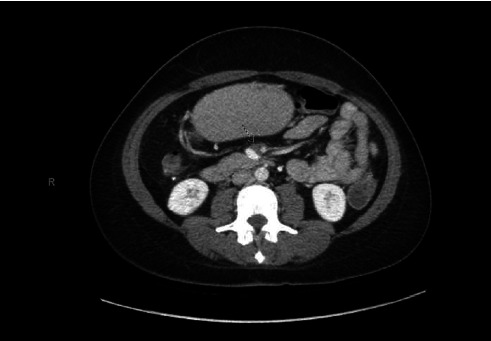

Colorectal cancer (CRC) continues to be a significant global health issue contributing to a high mortality rate. Despite advancements in treatment, the risk of recurrence remains due to inherent mutations and the rapid turnover of intestinal mucosa. We present an exceptionally rare case of CRC metastasis to the duodenum in a 42-year-old female who has been compliant with postsurgical surveillance. Despite previous negative surveillance results, elevated CEA levels and a 3-cm mesenteric mass were detected, raising concerns for carcinoma, which was later confirmed by biopsy. The tumor board deemed her ineligible for surgery due to vascular involvement, leading to palliative care and an attempt at neoadjuvant therapy. Vigilant monitoring is crucial for early detection and intervention.